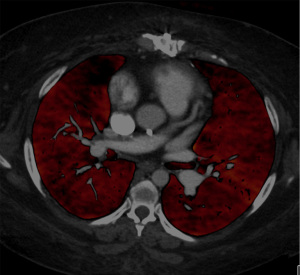

Chronic thromboembolic pulmonary hypertension (CTEPH) is a rare form of pulmonary hypertension (PH) that results from unresolved organized thromboemboli in the pulmonary arterial tree and is often precipitated by an acute pulmonary embolic event (1). Currently classified as Group 4 in the World Health Organization’s clinical classification of PH (2), CTEPH is characterized by thrombotic obstruction of pulmonary artery (PA) and subsequent vascular remodeling, leading to increased pulmonary vascular resistance (PVR) and eventual development of PH. The exact pathobiological mechanisms leading to CTEPH are still not completely elucidated. While predisposing conditions such as malignancy, chronic inflammatory disease, pacing wires and ventriculo-atrial shunts, antiphospholipid antibodies, splenectomy, thrombophilic disorder, and non-O blood group are known to increase the risk for CTEPH development, the exact transition from acute pulmonary embolism (PE) event to subsequent CTEPH development is still not fully understood (3). A unique feature of CTEPH is the development of secondary microvascular or small vessel disease (SVD). It is well known that microvascular disease is associated with poor surgical outcomes and persistent PH post-surgery (3). Imaging has proven to be transformative in diagnosis and treatment of CTEPH, with modalities such as ventilation-perfusion (V/Q) scanning and computed tomography angiography (CTA) being the mainstays in establishing the diagnosis (Figure 1). While macrovascular disease is well evaluated with imaging, preoperative evaluation of SVD still remains a diagnostic challenge. Many indirect findings on imaging studies can point to the presence of SVD although direct mapping of SVD still remains the holy grail in the management of CTEPH patients. This focused review aims to provide insights into imaging of SVD in the setting of CTEPH and highlight the challenges and future possibilities. We present this article in accordance with the Narrative Review reporting checklist (available at https://cdt.amegroups.com/article/view/10.21037/cdt-2025-1-652/rc).

DECT has revolutionized the imaging of CTEPH over the last decade. Using differences in iodine attenuation over different kilovoltages, DECT allows quantification of iodine within a voxel of lung tissue, termed as “perfused blood volume (PBV)”. Studies have shown PBV to be a good surrogate marker of lung perfusion (18). By allowing assessment of anatomic and perfusion information on a single scan, DECT has emerged as one of the frontline tools for assessment of CTEPH. Several studies have shown that perfusion information from DECT correlates with hemodynamic parameters and can help in prediction of post-operative outcomes (19-21). Qualitative assessment of PBV images can help identify areas of PSP and potentially identify patients with microvasculopathy (Figure 4). In a study 93 patients evaluated with DECT, pulmonary perfusion of blood volume in the normally perfused group showed an inverse correlation with PVR, while that of patients in the poorly perfused group did not. Patients with PSP on DECT had a lower diffusing capacity of the lungs for carbon monoxide (DLCO), which might be the strongest predictor of microvasculopathy including diffuse distal thrombosis (22,23). Another study demonstrated that PSP was present in 51% of patients with CTEPH, although this finding improved after BPA. Quantitative assessment of DECT-based vascular parameters might further insights into the presence of SVD, although data is lacking (24).